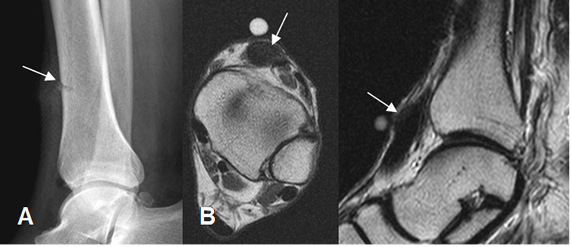

Fig 8. Retracción muscular.

A: Rx lateral. Fractura marginal de la tibia, secundaria a lesión por objeto cortopunzante.

B: RM axial en T1 y C: RM sagital en T2. Tendón del tibial anterior engrosado y retraído, por ruptura completa.